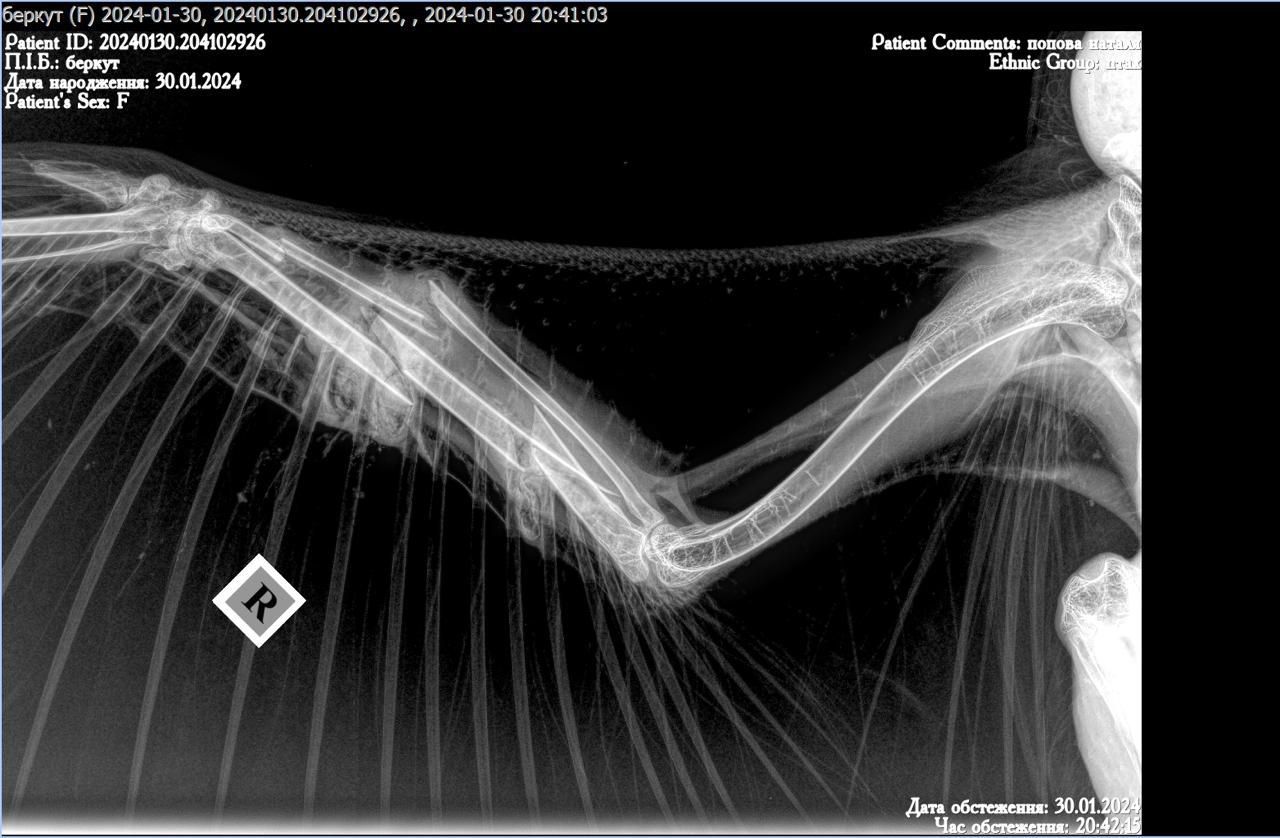

Діагностика показала перелом крила та інші проблеми з організмом птаха, які, очевидно, і знесилили беркута.